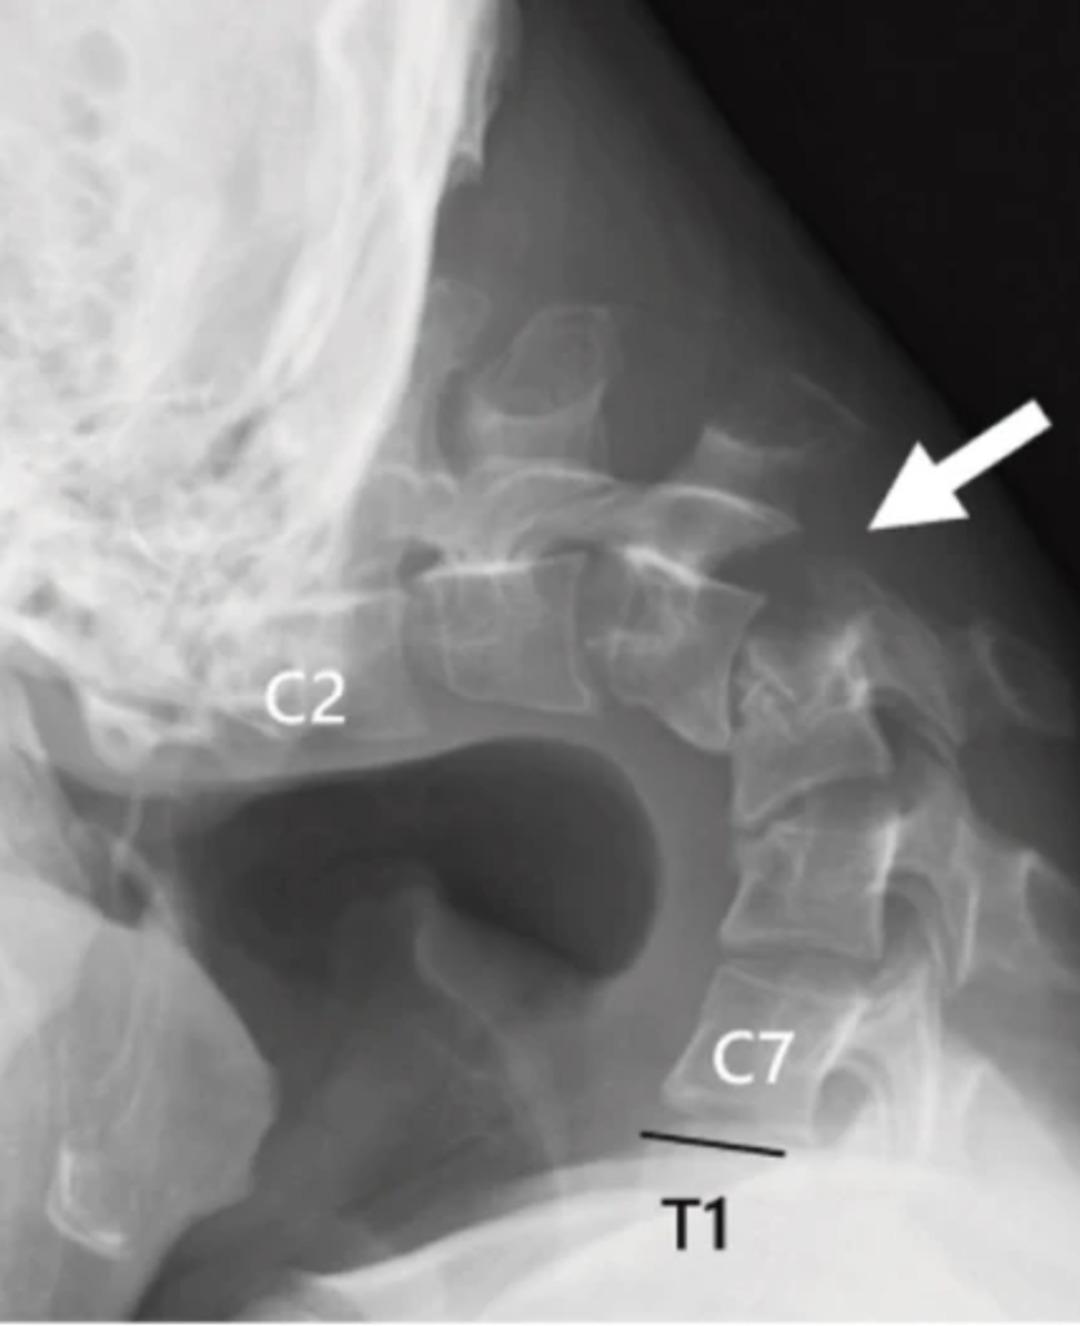

Sürekli bükülmüş pozisyon, genç adamın boynunun etrafında bir yumru oluşumuna yol açtı ve çene göğsüne dokunacak kadar bloke edildi. 2023’te hasta hızlı bir kilo kaybı yaşadı.

Yapılan sınavlarda omurgada ciddi hasar ve deformasyonlar tespit edilirken, boyun kasları işlevi kaybetti. Doktorlar eldeki müdahale ve kedinin yetersiz kullanımı için cerrahi çalışmaya karar verdiler.

Hasarlı omurlar ve kumaşlar çıkarılmış ve boynu hizalamak için metal vidalar ve çubuklar yerleştirilmiştir. Ameliyattan altı ay sonra hasta başını kaldırmaya başladı ve bir yıl içinde hareketliliğinin ve duruşunun önemli bir iyileşmesi gözlendi. Doktorlar, bu davanın genç yaşta ortaya çıktığını, “düşük kafa sendromunun” akıllı telefonların ve tabletlerin kullanımına bağlı olduğunu vurguladığını söyledi.